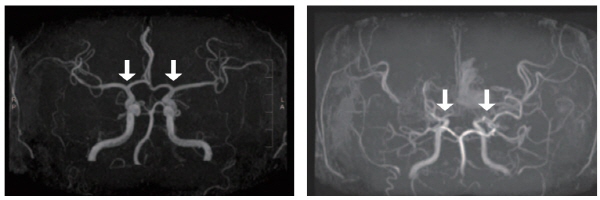

[사진 왼쪽부터] 정상 및 모야모야병 환자의 뇌혈관

모야모야병은 뇌로 혈액을 공급하는 혈관이 원인 없이 점차 좁아지는 만성 진행성 뇌혈관질환이다. 10세 전후 소아와 40세 전후 성인에서 주로 발병하며, 부작용으로는 뇌혈관이 막히거나 파열되는 허혈성·출혈성 뇌졸중이 있다. 그중 소아 환자는 성인보다 허혈성 뇌졸중이 빈번하고, 장기 예후가 대체로 양호하지만, 3세 미만 어린 연령에서는 진행이 빨라 주의가 필요하다. 그러나 국내 소아 모야모야병 인구를 분석한 장기간 역학 자료는 제한적이었고, 이들의 예후를 분석한 결과도 드물었다.